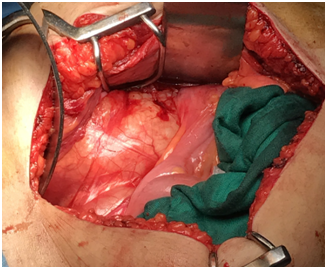

We present here the case of a 50-year-old woman who consulted for a mild right low back pain with palpable abdominal mass since several months. The clinical examination revealed a painless tumefaction of the right iliac fossa (Figure 1). A CT-scan performed showed a large right retroperitoneal cystic polylobed mass, well limited, measuring 15 cm x 10 cm x 9 cm, pushing forward the digestive loops and pushing up the right kidney, containing calcifications, without enhancement after contrast injection, and without evidence of adjacent structures infiltration, evoking a retroperitoneal cystic lymphangioma (Figure 2) and (Figure 3). The patient underwent an exploratory laparotomy, which showed a large whitish retroperitoneal cyst, extending from the right iliac fossa to the right hypochondrium (Figure 4). Given the appendix was not individualized, we suspected then, during surgery, an appendiceal mucocele. During dissection, we assisted to a tumoral rupture, and approximately 500 milliliters of a thick, gelatinous mucoid substance was sucked. The peritoneal cavity was already protected by surgical drape. We went an en-bloc and complete resection of the tumor (Figure 5). The post-operative course were normal. The histological study concluded to a mucinous cystadenoma (Figure 6). After a one-year follow-up, control CT-scans showed no signs of recurrence.

Figures 4 Protrusion of the tumor in the peritoneal cavity.